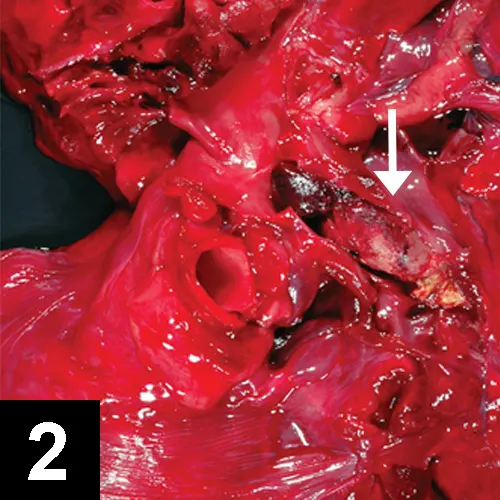

FIGURE 2

Thrombus (arrow) in pulmonary artery

• Postmortem findings may show in situ thrombus (Figure 2).